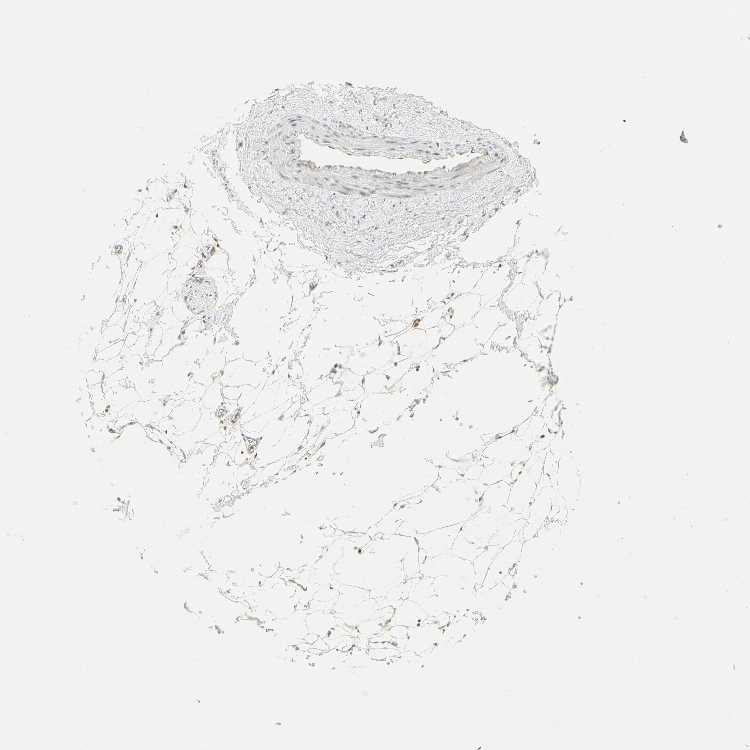

SOFT TISSUE 2 - Antibody stainingi

Antibody staining in the annotated cell types in the current human tissue is reported as not detected, low, medium, or high, based on conventional immunohistochemistry profiling in selected tissues. This score is based on the combination of the staining intensity and fraction of stained cells.

Each image is clickable and will lead to virtual microscopy that enables deeper exploration of all samples and also displays staining intensity scores, fraction scores and subcellular localization as well as patient and tissue information for each sample.

Antibody HPA006916Antibody HPA010568Antibody CAB017617

Fibroblasts -LowMedium

Peripheral nerve MediumLowMedium